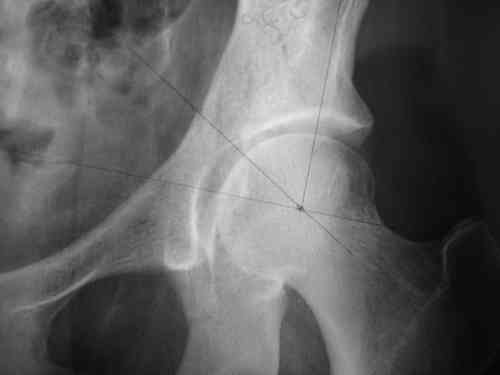

прилагаю пример с такой же давностью травмы, репонировали аппаратом

> R-негативного стола. Зато новый ЭОП. Как вы проводите илиосакральные

> винты? хотябы кратенько методику.

стаскиваете пациента вниз, кладете под ноги какую-нибудь подставку, а дальше как обычно, можно , например, прочитать здесь